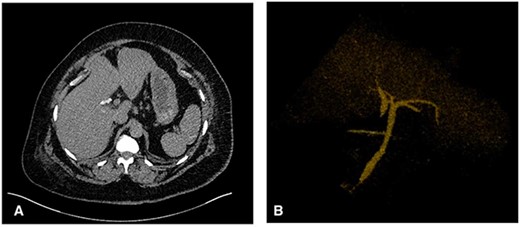

Different variants of extrahepatic biliary tree anomalies have been encountered, typically intraoperatively at cholangiogram inciting the development of various classification systems of CBD duplications and aberrant right hepatic ducts [7, 8]. Amongst these, duplicated CBDs are the rarest which often include variations of duplicated CHDs that are always accompanied with duplicated CBDs (Fig. 4) [6]. Our case shows a duplicated CHD draining the right intrahepatic system with its counterpart draining the left and a communicating aberrant duct in between. A similar variant has been encountered only once in the literature in a 13-year-old male presenting with chronic epigastric pain and subsequent jaundice [5]. Despite the rarity of comparable variants, it is important to understand them owing to the risk of iatrogenic CBD injury [9]. The overall incidence of iatrogenic CBD injuries at LC has remained stable over the past three decades at 0.3% with current evidence suggesting that 80% of these injuries are due to a misinterpretation of biliary tree anatomy [10].

Duplicated CBD classification developed by Researchers E. Choi, J.H. Byun, D. Park et al. (2007). Type IIIa – Type Vb variants have duplicated CHD and CBD ducts with Type V duplications the rarest.